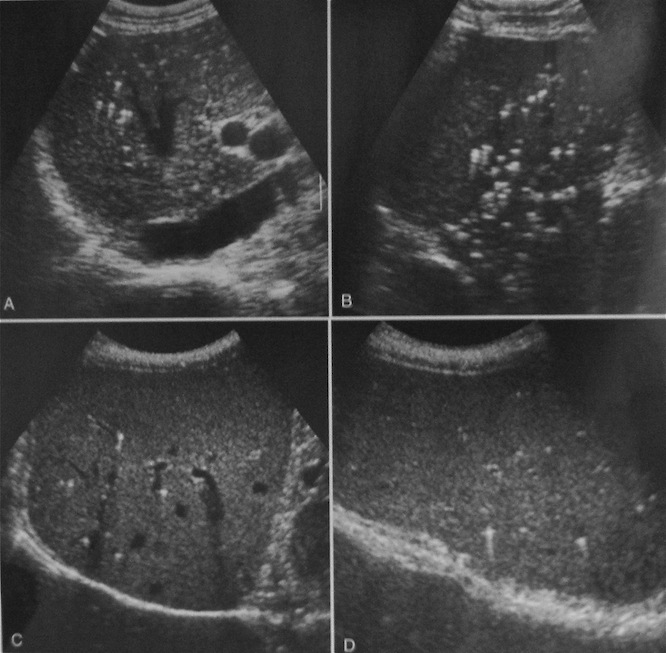

Внутрипротоковые гамартомы

Здесь немного другое. На приведенной Вами эхограмме, как мне кажется, эхогенность паренхимы немного диффузно снижена, что привело к выделению сосудистого рисунка. В обсуждаемых эхограммах - какие-то конкрементоподобные структуры видимо в мелких протоках. Ждем верификации.

Да, уважаемый ФАМ оказался прав - это внутрипротоковые гамартомы - спасибо Марио.

Что теперь можно смело писать - "множественные гамартомы внутрипеченочных протоков", если встретится такая картина, а она и у меня не раз встречалась?